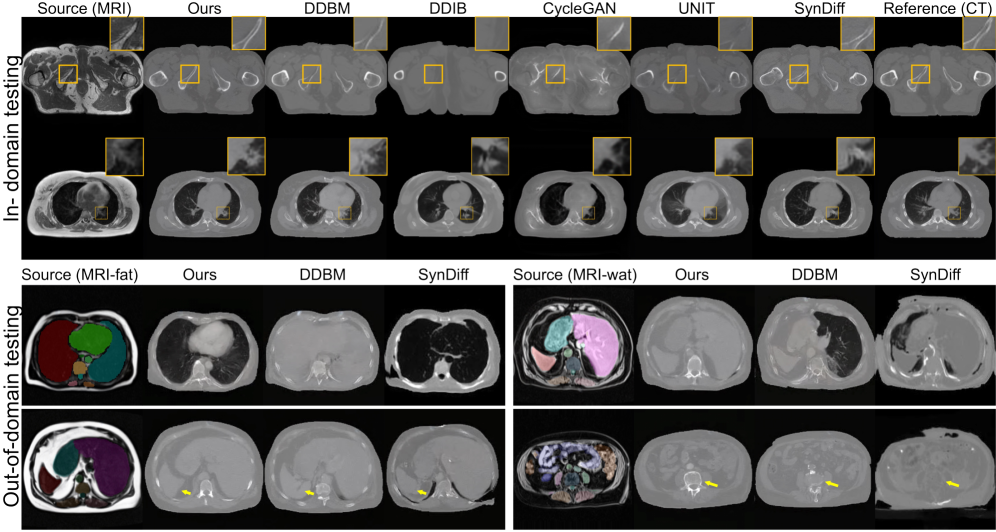

Refer to caption

Figure 4: Our SSB ensures anatomically consistent MRI\rightarrowCT translation across in-domain and out-of-domain scenarios. Segmentation masks are overlaid on MRI source images in OOD settings to provide structural reference, as paired CT ground truth is unavailable. They are not used during training or inference and serve only to illustrate anatomical fidelity without segmentation supervision.

We compare our method against representative baselines widely used in medical I2I translation, including GAN-based models CycleGAN Zhu et al. (2017) and UNIT Liu et al. (2017), zero-shot diffusion approaches SDEdit Meng et al. (2022) and DDIB Su et al. (2023), and the hybrid CycleGAN–diffusion framework SynDiff Özbey et al. (2023a). Since edge-based representations, such as Canny edges, are commonly used in MRI–CT translation—where diffusion models learn to reconstruct images from edge maps in a self-supervised manner Chen et al. (2024)—we additionally implement a DDBM variant using Canny edges. This comparison demonstrates that DINO-based embeddings capture richer geometric and semantic information than handcrafted edge filters. Fig. 4 and Table 1 present qualitative and quantitative results on in-domain and OOD MRI\rightarrowCT translation. Since no paired CT is available, we compute FID against CT scans from the training set and MS-SSIM between the input MRI and the synthesized CT as a proxy for structural similarity. We also provide qualitative results and segmentation overlays, with additional visuals in the Appendix. Our method shows stronger robustness to new MRI contrasts and achieves more accurate translations than SynDiff and DDBM, preserving geometry and modality realism.